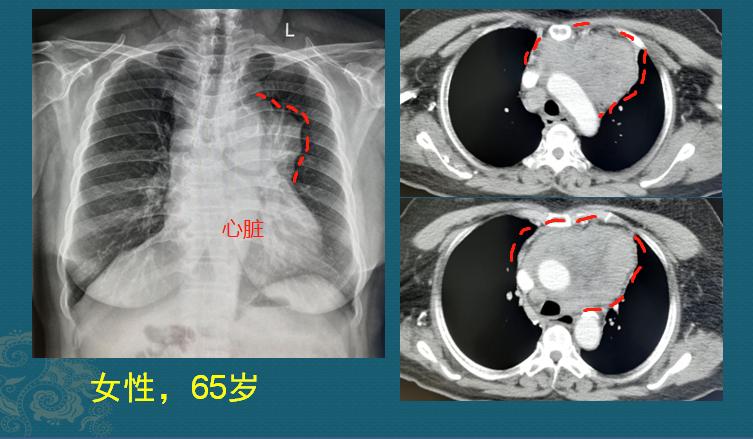

一位65岁女士,反复咳嗽1个月,过来拍胸部X光片,发现左侧肺门区肿块:

真不好说!这个肿块紧挨着纵隔和肺门,有些小病灶早期容易被大血管挡住,如果是胸透或者胸部x光片体检,难免会发生漏诊。

病人又做了个增强CT,果然发现了前纵隔巨大肿块:

如上图红线所示,肿块位于胸骨后的前纵隔,已经长到9.0×8.0cm,并且像八爪鱼一样包绕大血管生长,提示为恶性肿瘤(良性肿瘤多膨胀性生长,推移周围血管结构;恶性肿瘤常包绕并侵犯周围结构),且已经无法切除,属于晚期了。

大家可见从上面的CT片可以看到,肿块主体位于前纵隔(胸骨后方、心脏大血管前方),常见的疾病包括胸腺瘤/胸腺癌、胸腺囊肿、胸腺脂肪瘤、纵隔淋巴瘤、纵隔生殖源性肿瘤、胸内甲状腺肿瘤及肿瘤样病变;胸部CT是纵隔影像检查的最主要方法。

这个病灶我们考虑胸腺癌,鳞癌可能大,依据有下面几点:

4.胸腺恶性肿瘤与肺界面通常比较光滑(上图红线),一般不侵犯临近肺组织,但淋巴瘤常见侵犯临近肺组织,并多见心包积液和胸腔积液。

这位女士后来做了纵隔肿瘤穿刺,确诊为胸腺癌(非角化型鳞癌)。因为已无手术机会,正在寻求其他治疗方法。

而她每年的体检项目,肺部检查都是简单的胸透,没有选用胸部螺旋CT。如果是胸部CT体检,是有机会早期发现并治愈的!